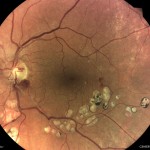

TrueColor共焦点技術

画角 45°の網膜画像

TrueColor共焦点技術は、白色光LED光源を使用し、白内障眼でも詳細な画角 45°の網膜画像を撮影することが出来ます。